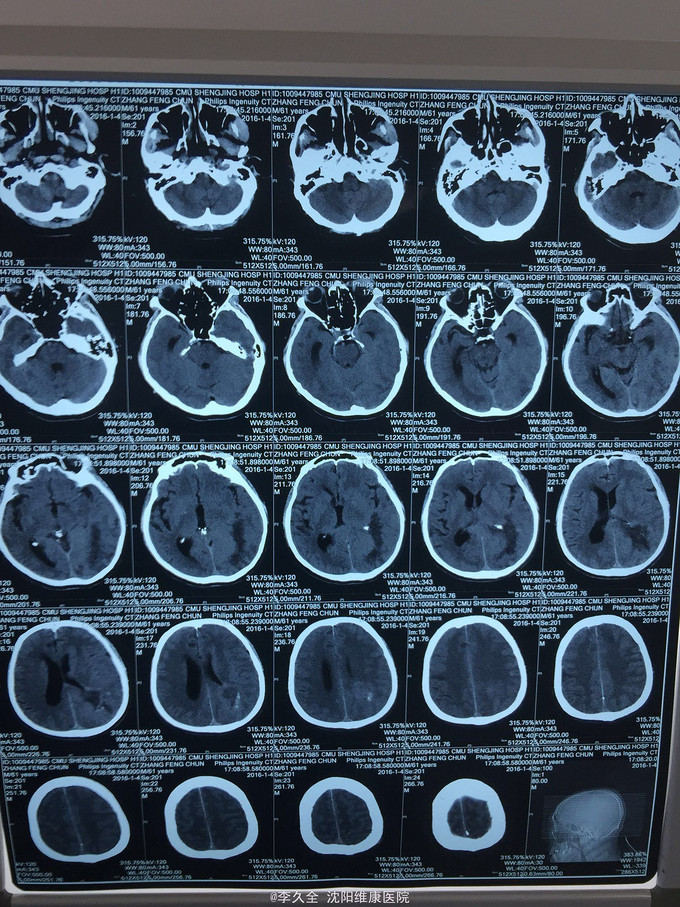

男,62岁,以头晕、视野缺损、记忆力减退、失写、失算7个月入院! 现病史:去年7月出现头晕,就诊于医院,行头CT:代诉未见异常,口服药物无效,后出现右侧视野缺损,走路撞墙、撞门,就诊于当地医院、北京协和医院,考虑“㬵质瘤”,近3个月出现近事遗忘为主,平时写字不会,计算力下降,不认识人! 既往史:2型糖尿病5年!

查体:BP:150/80mmHg,心肺腹无异常。神清,不能言语,失写、失算、失认,双曈孔等大正圆,直径3.0mm,光敏,四肢能够活动,右侧肌张力增高,巴氏征R+L-,颈强3横指,克氏征阳性! 影像MR:

1.颅内占位,胶母可能大! 2.2型糖尿病